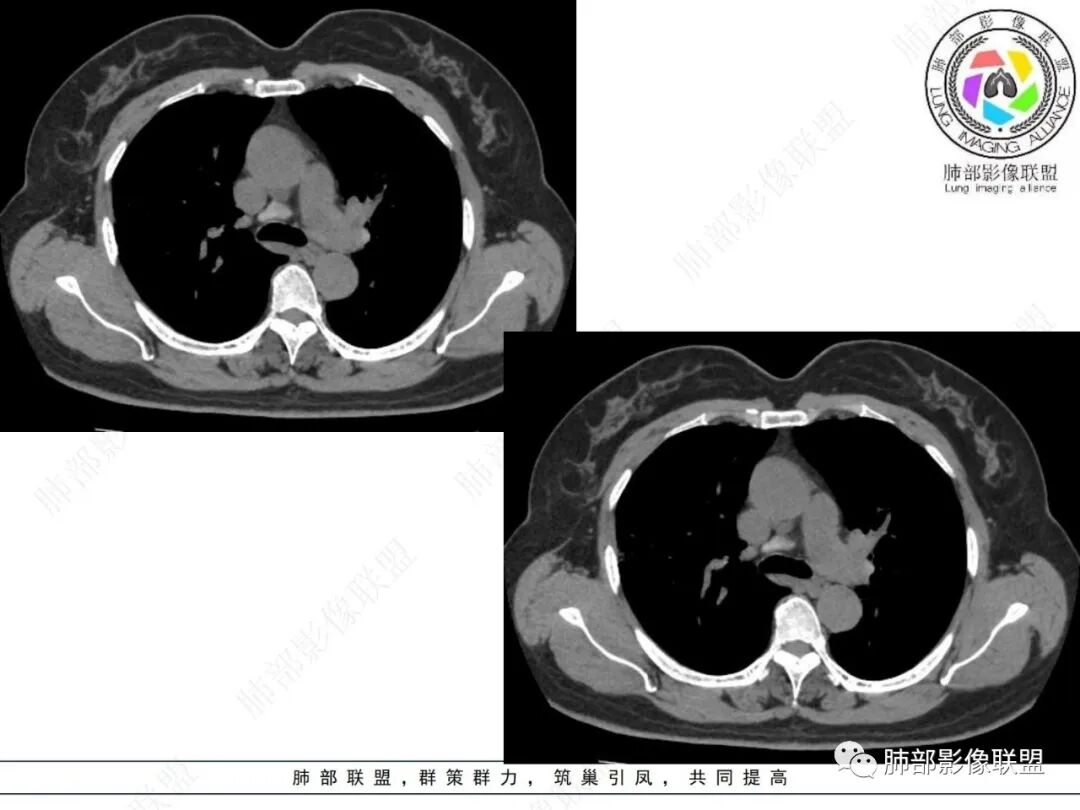

1.临床特点:57岁女性,体检发现阴影。

2.影像特点:

右肺上叶胸膜下混合磨玻璃团片影。

周围磨玻璃部分间杂条索状高密度区,密度欠均匀(可疑重力分布趋势),其磨玻璃影边界大多较清楚或可分辨,部分“L型”边缘,提示小叶间隔阻挡可能。血管穿行自如,可疑远端支气管进入。

实性部分较密实,不规则,隐约见棘突或刺状突起,未见钙化、空洞或液化区,实性边缘可见斑状略低密度间隙(借用王兆宇老师课件,称其呈“松软”的形态)。动脉期实性部分较明显不均匀强化,如果有完整增强图,还可以观察内部血管情况。

纵隔窗相对肺窗病灶相对小,仅部分实性影呈现。病灶张力不高,相邻胸膜增厚(糊墙),未见明显胸膜牵拉凹陷。

未见卫星病灶,远处未见磨玻璃结节影。

双肺门及纵隔未见明显增大淋巴结。心包及胸腔未见积液。